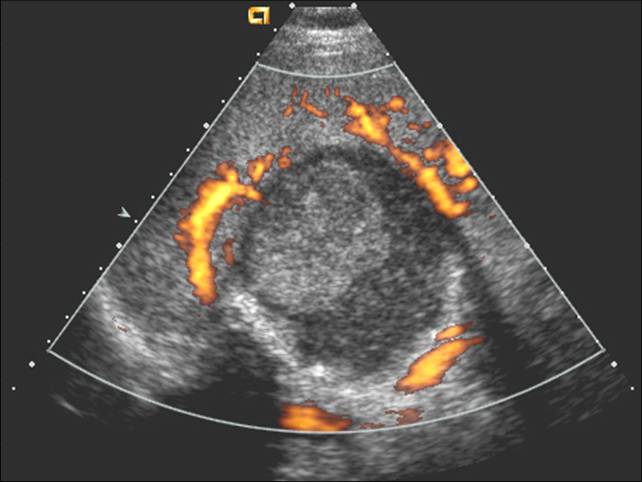

彩色多普勒

无血流信号

超声造影

无增强

假性脾囊肿: